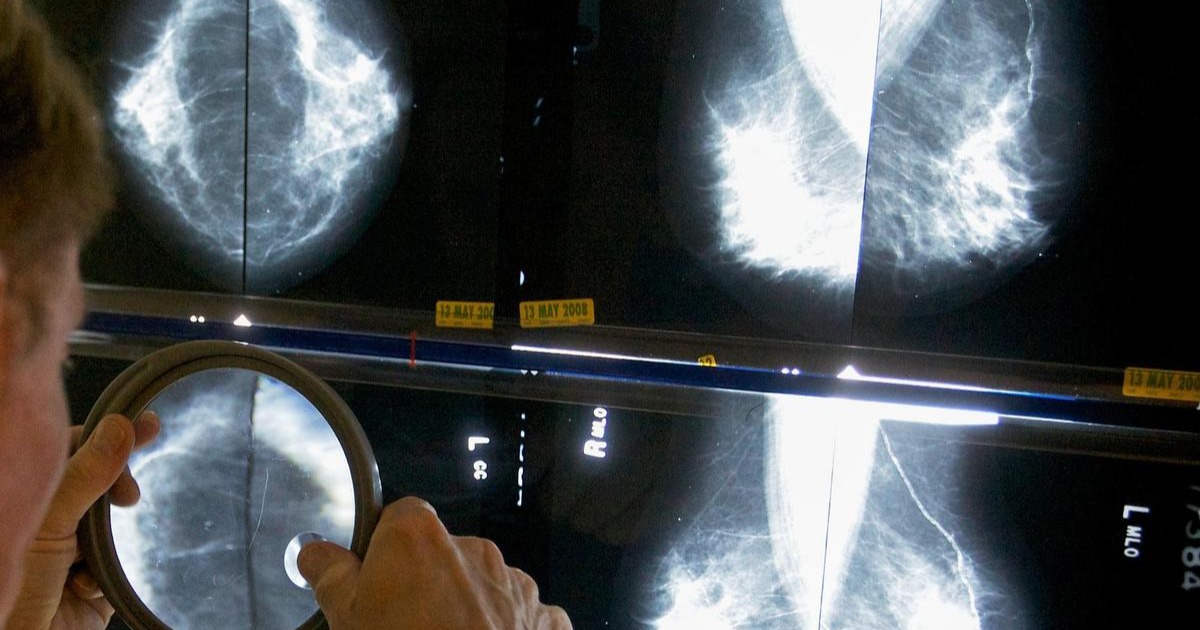

30 വർഷം, ഇരട്ടിയിലധികം കേസുകൾ: ഇന്ത്യയിൽ സ്തനാർബുദം പടരുന്നു

ഇന്ത്യയിൽ കഴിഞ്ഞ 30 വർഷത്തിനിടെ സ്തനാർബുദ കേസുകൾ ഇരട്ടിയിലധികമായി വർധിച്ചതായി ആരോഗ്യ വിദഗ്ധർ. കൊൽക്കത്തയിൽ നടന്ന അന്താരാഷ്ട്ര ഓങ്കോളജി കോൺഫറൻസിലാണ് രാജ്യത്തെ ആശങ്കപ്പെടുത്തുന്ന കണക്കുകൾ പുറത്തുവിട്ടത്. 1990-കളിൽ ഒരു ലക്ഷം സ്ത്രീകളിൽ 13 പേർക്ക് എന്ന നിലയിലായിരുന്ന രോഗസാധ്യത, 2023-ഓടെ 29.4 ആയി ഉയർന്നുവെന്ന് സെന്റ് ഗാലൻ ഇന്റർനാഷണൽ ബ്രെസ്റ്റ് കാൻസർ കോൺഫറൻസിന്റെ ഇന്ത്യാ പതിപ്പിൽ വിദഗ്ധർ ചൂണ്ടിക്കാട്ടി.

സ്ത്രീകളിലാണ് രോഗസാധ്യത കൂടുതലെങ്കിലും പുരുഷന്മാരിലും സ്തനാർബുദം കണ്ടുവരുന്നുണ്ടെന്നും, കൃത്യമായ ഇടവേളകളിൽ ഇരുലിംഗക്കാരും പരിശോധനകൾ നടത്തേണ്ടത് രോഗം നേരത്തെ തിരിച്ചറിയാൻ അത്യന്താപേക്ഷിതമാണെന്നും സമ്മേളനം ഓർമ്മിപ്പിച്ചു.